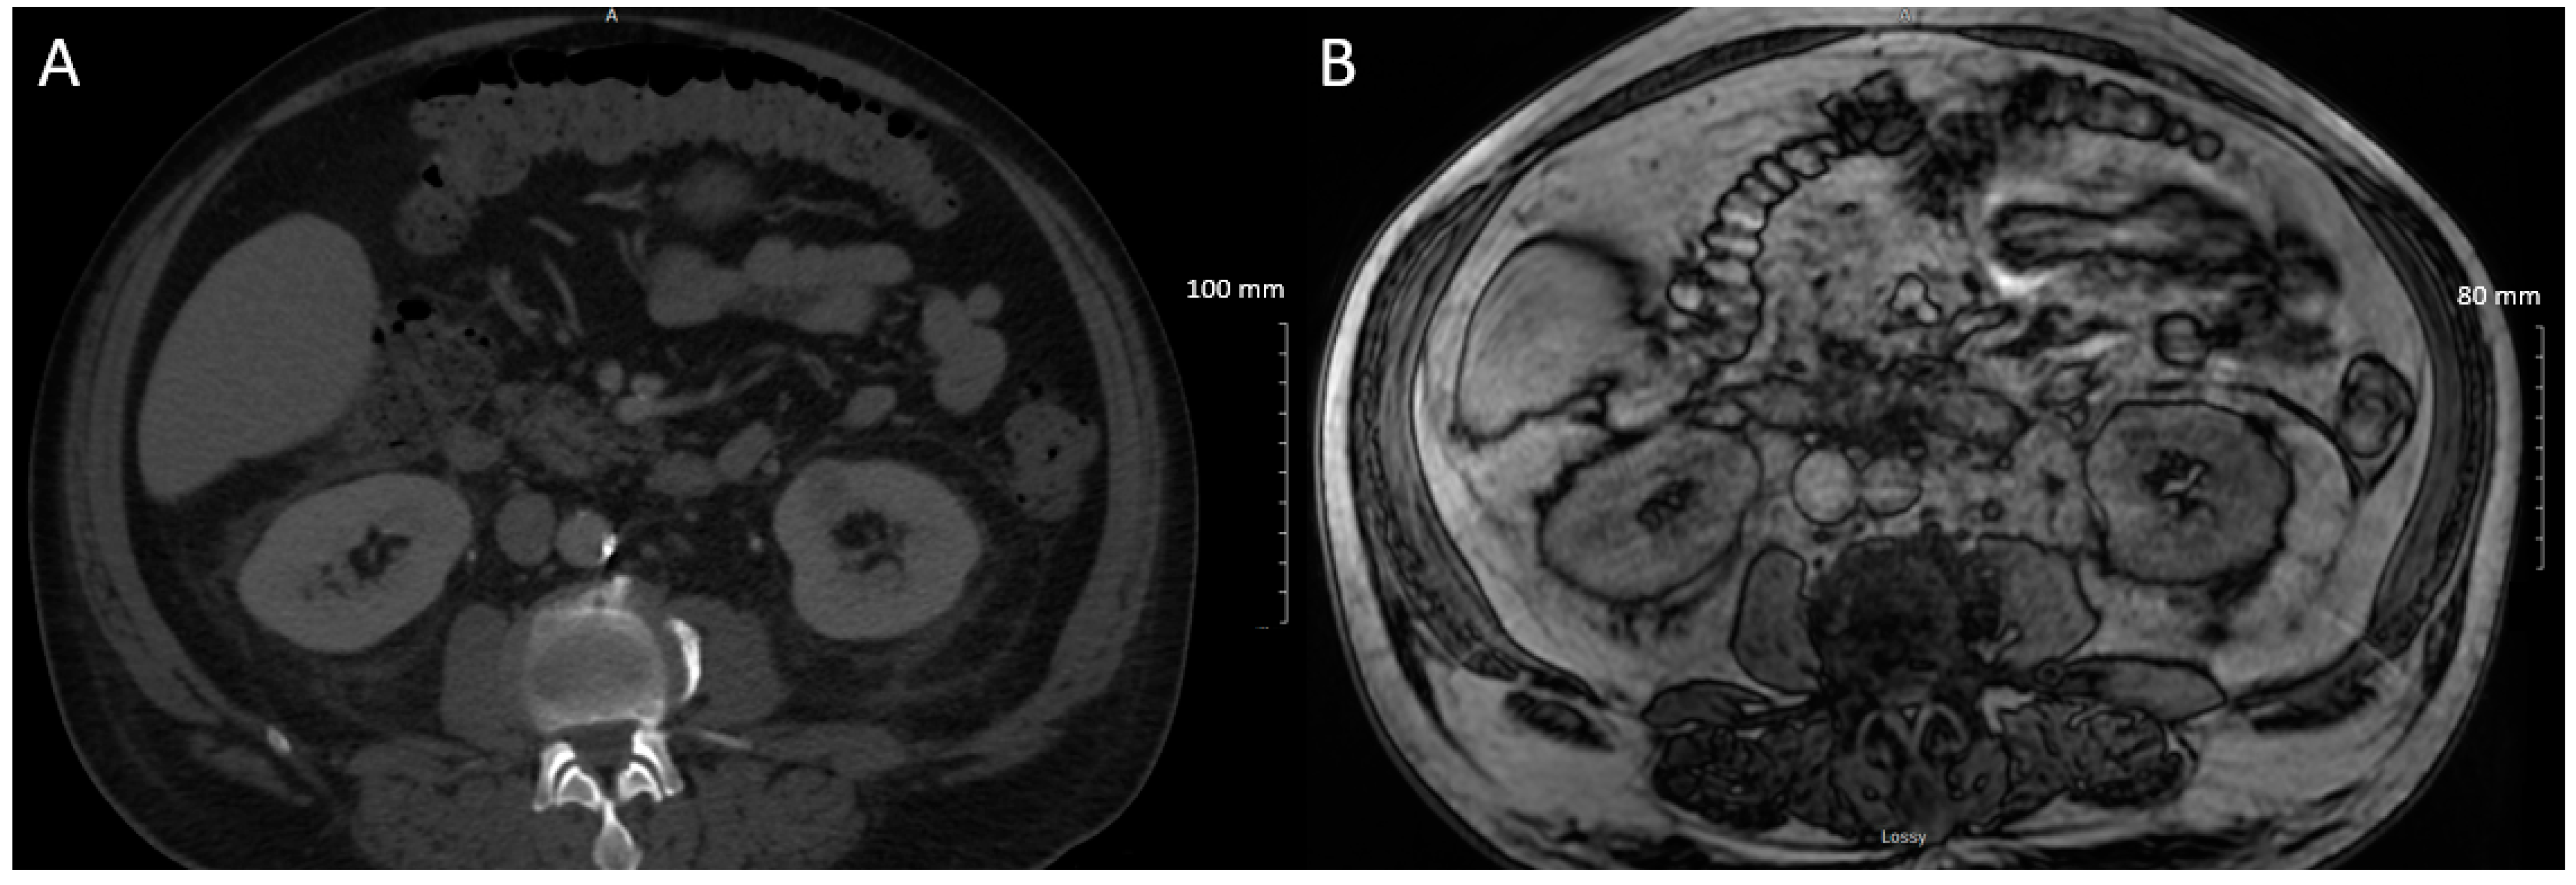

2. Case